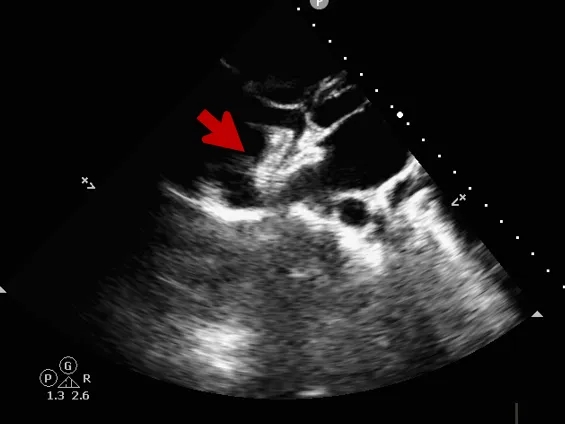

锁定后评估

心尖四腔心切面可见封堵器形态良好

主动脉短轴切面可见封堵器呈“Y”字型抱住主动脉

彩色多普勒血流成像显示无残余分流存在

释放后评估

封堵器位置正确、形态良好

封堵成功